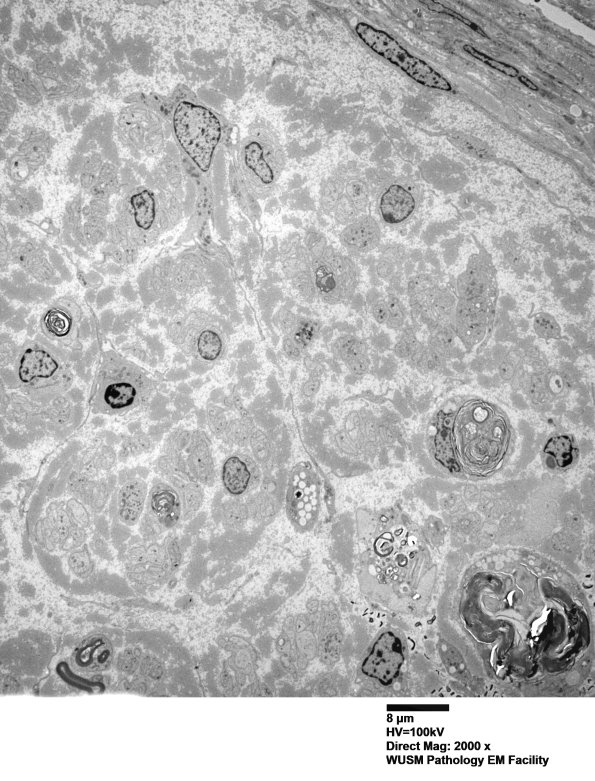

Much of the fascicle looked very axon depopulated with some residual debris and a few ongoing degenerating axons. (electron micrograph)